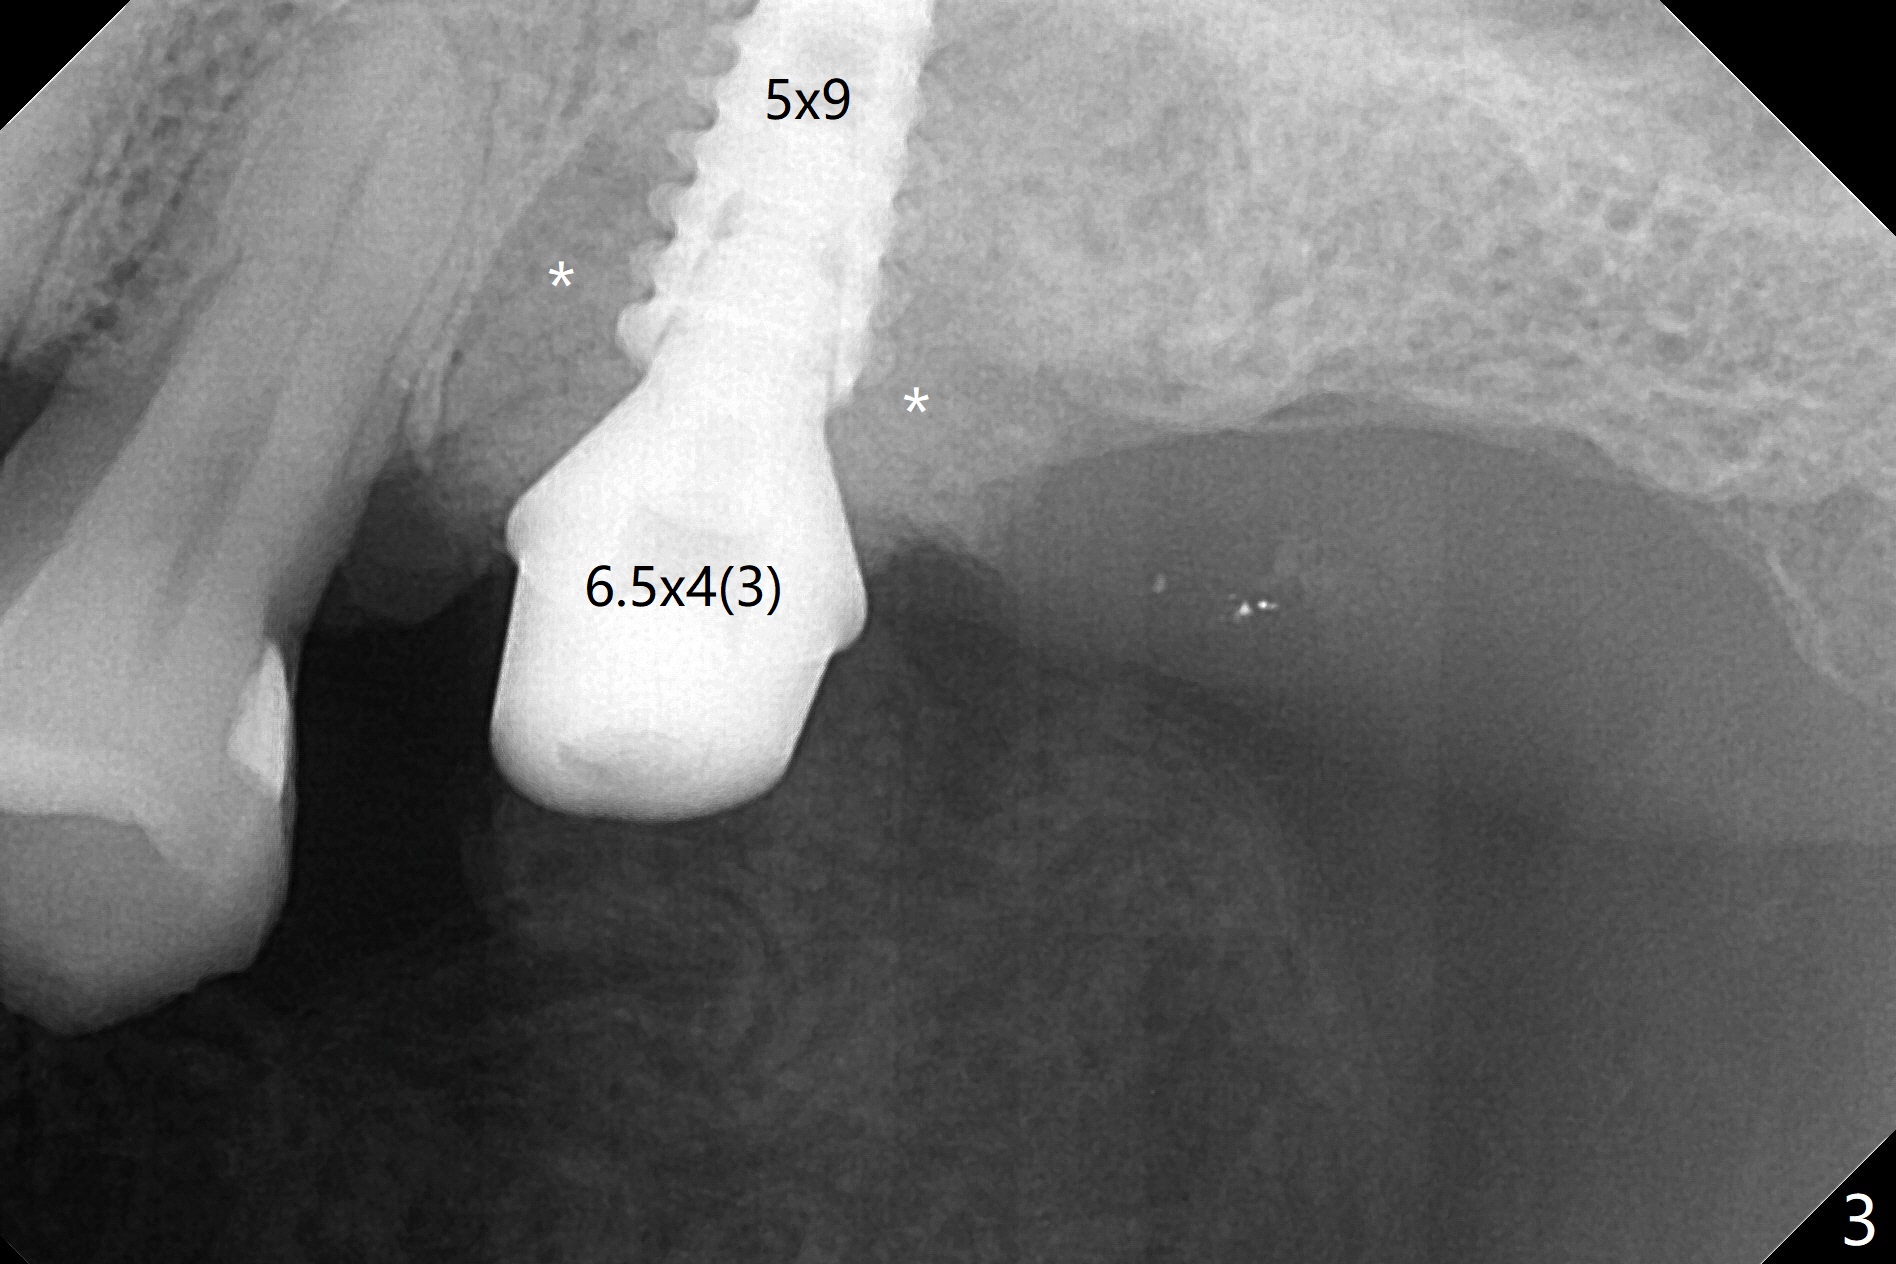

After extraction of the tooth #14 (Fig.1) and removal of granulation tissue associated with a distal fistula, a 1.6 mm drill is used to initiate osteotomy in the septum for 9 mm, followed by insertion of a 7 mm long parallel pin (Fig.2).  The length of the subsequential osteotomy is 11 mm until 4.8 mm in diameter (overprep as will be shown below).  The bone is hard so that sinus lift fails with 4.8 mm Magic Expander.  Since a 5x9 mm dummy implant is placed with stability, a definitive implant with the same dimension is chosen with >50 Ncm (Fig.3,4).  Prior to and after abutment placement, Vera graft is placed (*).  The provisional perforates with loose abutment 3.5 months postop.  A 6x4 mm healing abutment is placed.  Osteointegration occurs 4 months postop (Fig.5,6).